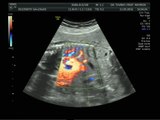

הריון שני - שבוע 23 סקירת מערכות מאוחרת 11.5.2016